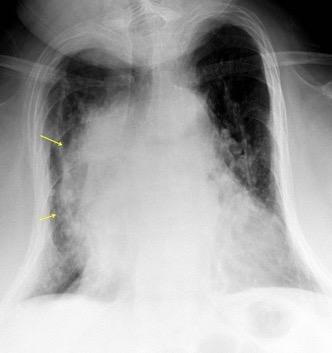

59. CUERPO VERTEBRAL. AFECTACIÓN CON MASA

62. LÍNEAS PARAESPINALES. DESPLAZAMIENTO BILATERAL DE

Mieloma múltiple

Ganglios. (LLC, linfoma)

Osteofitos/ Lipomatosis

Fibrosis

Espondilodiscitis